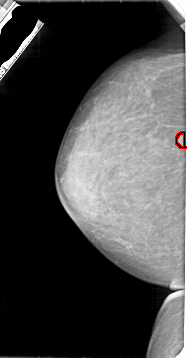

A_1947_1.RIGHT_CC

RIGHT_CC LINES 5116 PIXELS_PER_LINE 2551 BITS_PER_PIXEL 12 RESOLUTION 43.5 NON_OVERLAY

FILE: A_1947_1.LEFT_CC.OVERLAY

TOTAL_ABNORMALITIES 1

ABNORMALITY 1

LESION_TYPE MASS SHAPE ROUND MARGINS CIRCUMSCRIBED

ASSESSMENT 3

SUBTLETY 4

PATHOLOGY BENIGN

TOTAL_OUTLINES 1

BOUNDARY